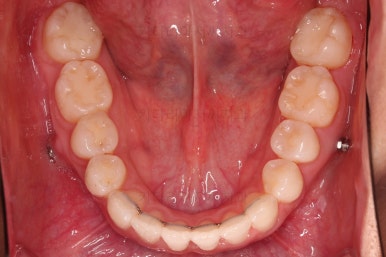

종료 시 사진입니다.

중앙선, 교합, 치아배열 모습 모두 양호해졌습니다.

상하좌우 총 4개의 미니스크류를 이용해서 치열을 뒤로 당겨줍니다.

중간평가를 하면서 환자분과 가능한 수준/원하는 수준을 잘 조율해 가면서 입매를 정해갑니다.